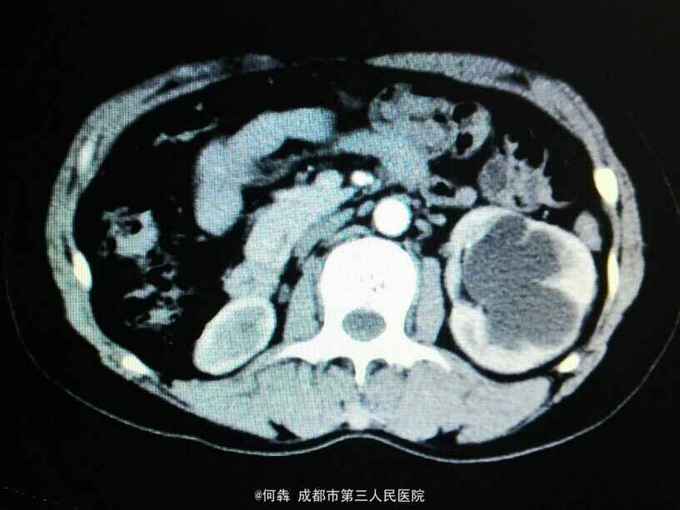

左肾区轻叩痛。尿常规:白细胞72个/ul。CT见图片。左侧GFR42.27,右侧GFR14.46。

左肾盂输尿管交界处结石 左肾重度积水,左肾结石,右肾萎缩,尿路感染。